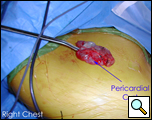

手術室では、全身麻酔と一つの肺換気の下で、胸腔鏡が右中顎線と第7肋間腔に導入された(下のビデオ1)。 嚢胞は、約9x6cmを測定し、右心膜の前外側の側面で容易に視覚化された(図3)。 嚢胞の後方に横隔神経を認めた。 第4肋間腔の前腋窩線に第二の切開を行った。 リングクランプを用いて嚢胞を把握した(図4)。 第5肋間腔の肩甲骨ラインに第三の切開が行われた。 胸腔鏡下はさみと焼灼術(心臓不整脈の可能性を最小限に抑えるために低い設定で)は、心膜から嚢胞を解剖するためにそのポートを介して使用された(図5)。 嚢胞と心膜腔との間の接続が同定された。 それは小さく、はさみで分割されました。 嚢胞の後面の解剖により除去が完了した。 横隔神経は常に明瞭に視覚化されていた。 病理報告では、良性の中皮内嚢胞の診断が確認されました(図6)。

| 図5. 横隔神経を視野に入れた嚢胞切除術を施行した。 | 図6。 切除標本 |